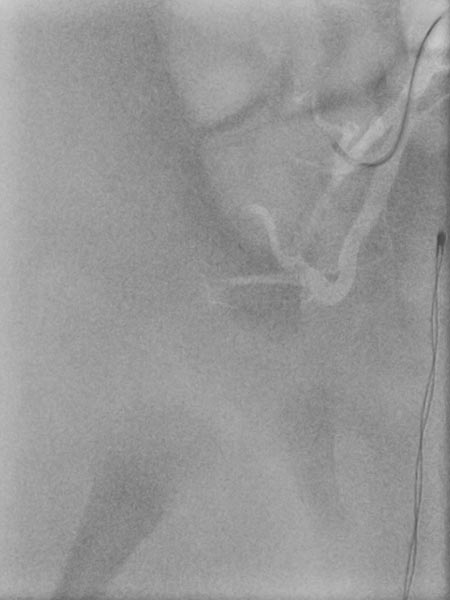

In view of massive coagulopathy prohibiting open surgery in this location and lack of improvement with drug therapy and replacement of platelets and coagulants alone, the decision was made to embolize the hypervascularized tumor. Digital subtraction angiography (DSA) shows the highly vascularized tumor supplied mainly from the right superior gluteal artery.

The tumor shows the typical tumor blush with diffuse, strong contrast enhancement on DSA after super-selective catheterization with the microcatheter.

Via the microcatheter, the tumor is now gradually embolized super-selectively with particles 150 microns in size via the supplying arterial branches.

In the control DSA, the main part of the tumor has now been successfully embolized and cut off from the circulation. Only very cranial tumor-supplying branches remained at this stage of the embolization.

These very cranial parts are now also catheterized super-selectively with the microcatheter and embolized with particles. For better navigation of the microcatheter, the vessels from a previous injection are electronically overlaid by the computer (so-called “overlay display”, white in the image).